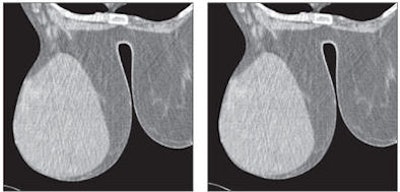

![]() |

| Fifty-eight-year-old woman with phyllodes tumor in left breast. Dynamic MDCT scans at baseline (left) and one minute after contrast administration (right) show a large, regular lesion with early and intense enhancement in most of the breast. All images courtesy of the American Roentgen Ray Society. |